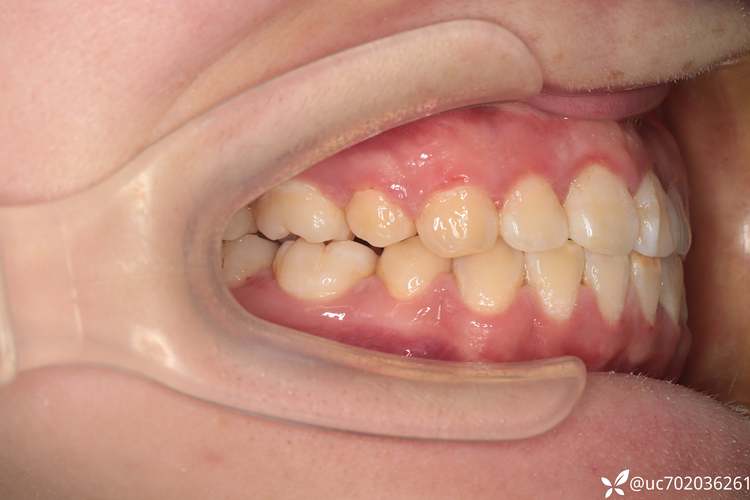

(图片来源网络,侵删)